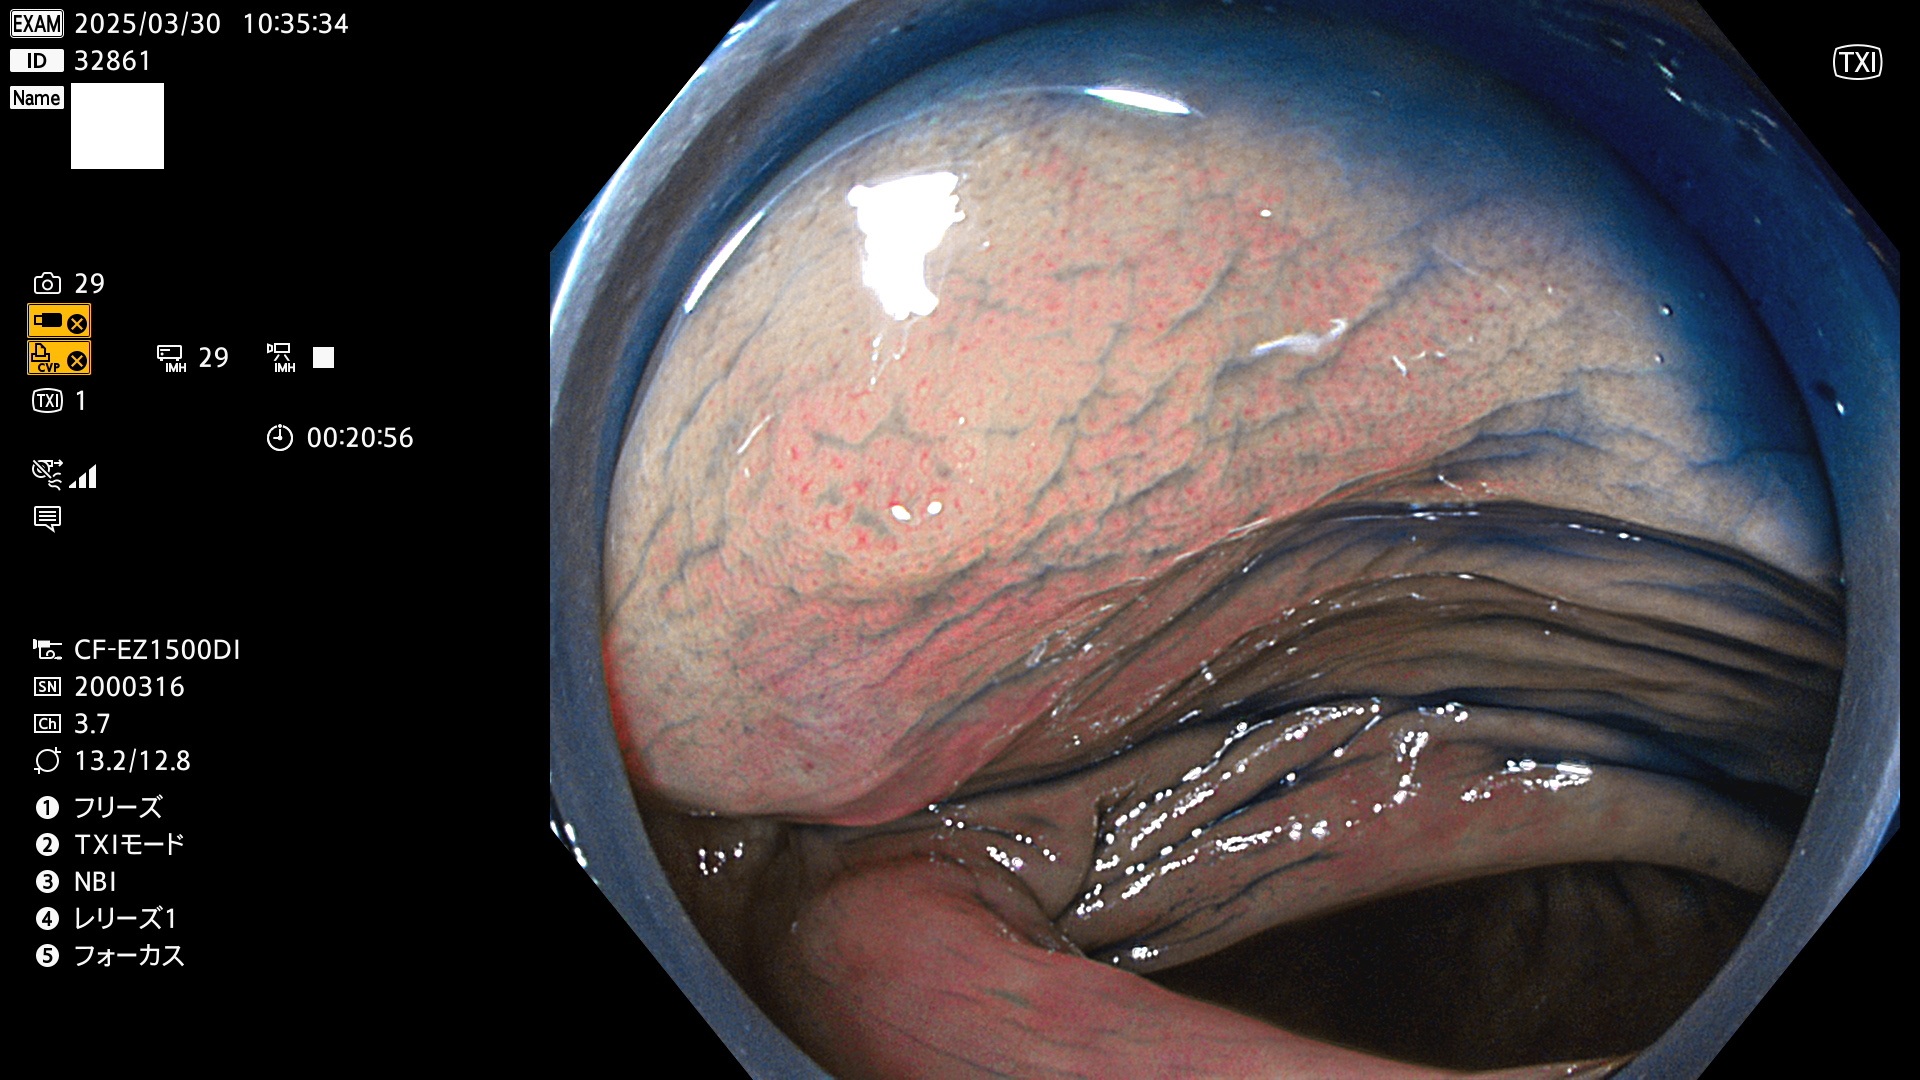

抽出の対象期間 2025年3月27日〜3月30日の4日間(48件の検査)8個 (8/48=16%)